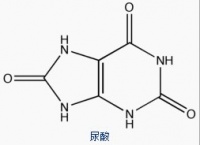

嘌呤,主要以嘌呤核苷酸的形式存在,它在能量供应、新陈代谢的调节及组成辅酶等方面起着十分重要的作用。嘌呤(包括腺嘌呤C、鸟嘌呤G)是构成核苷酸的物质基础,核酸(即我们熟知的DNA,RNA)为生命的最基本、最重要的物质之一,核酸则是由许多核苷酸聚合而成的生物大分子化合物。它们之间的关系是:嘌呤是核酸氧化分解的产物,而尿酸是嘌呤代谢的产物(2,6,8--三氧嘌呤)。

因此并非是嘌呤、尿酸导致的痛风,准确地说是核酸氧化分解出--嘌呤-氧化成(2,6,8--三氧嘌呤)-即尿酸等物质的代谢紊乱才是痛风的病理实质。